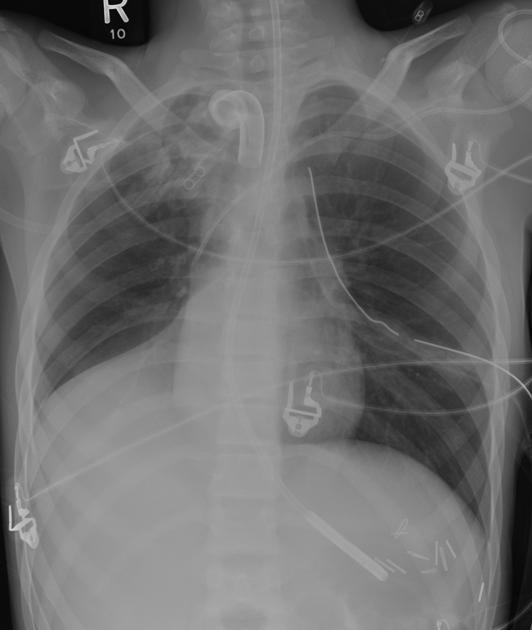

Comment on this CXR

Right lower lobe collapse